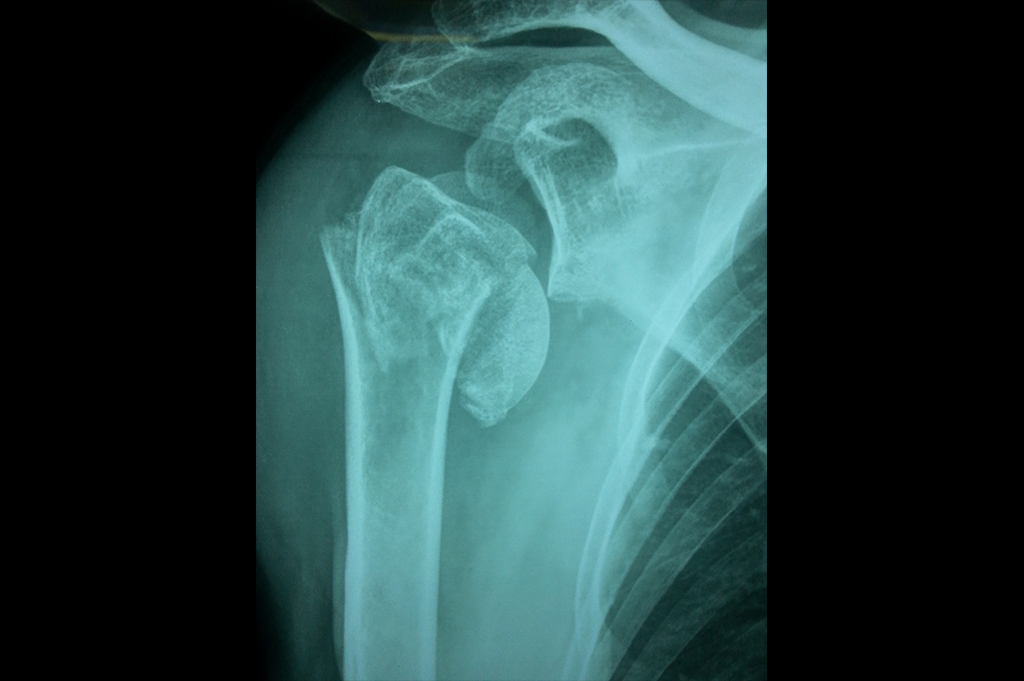

Proximal Humerus